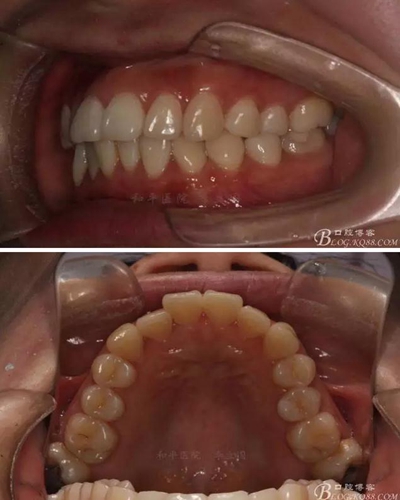

如圖,該病例為簡單排齊病例,但77鎖合是矯治中的關(guān)鍵所在,你會怎么處理?

該病例主要為17、27頰側(cè)位同時伴有伸長,當(dāng)然種植支抗可以解決,但還有簡單實用的辦法嗎?如圖,在橫腭桿遠中延伸出牽引鉤,位置盡量遠離合平面,7粘舌側(cè)扣,牽引力的方向為壓低及舌向,下圖為兩個月的效果,17已到位,27還未到位。